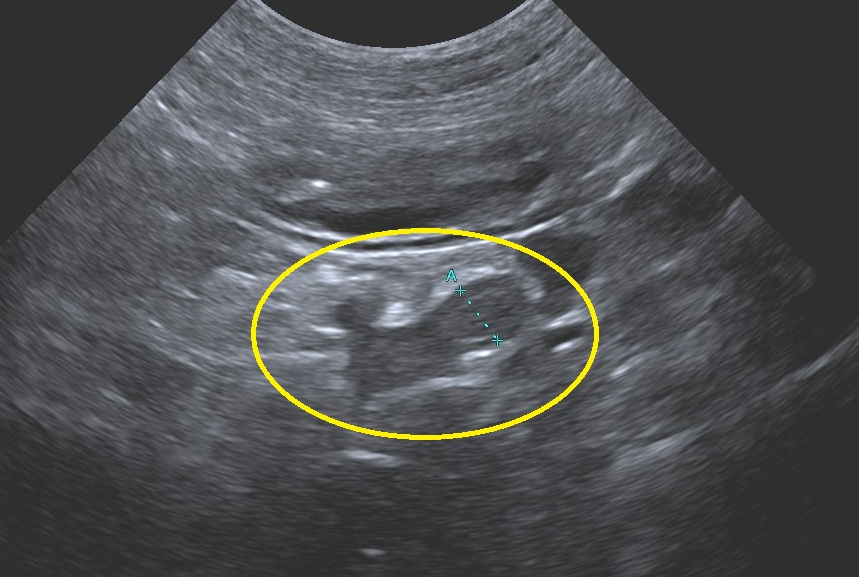

実際の超音波検査画像です。

黄色で囲ったひょうたん型のものが

副腎です。

副腎が大きくなっていると

クッシング症候群を疑います。